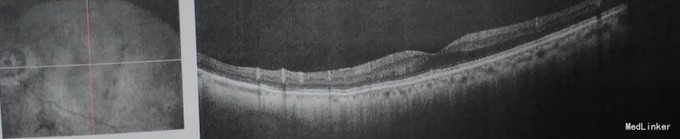

查体: VOD 0.9,VOS:0.8,双眼中央前房4CT,周边1/2CT,虹膜纹理清,瞳孔3×3mm,晶体混浊++。眼底 C/D约0.8。双眼房角开。 辅查: 右眼视盘视神经纤维层下方厚度变薄